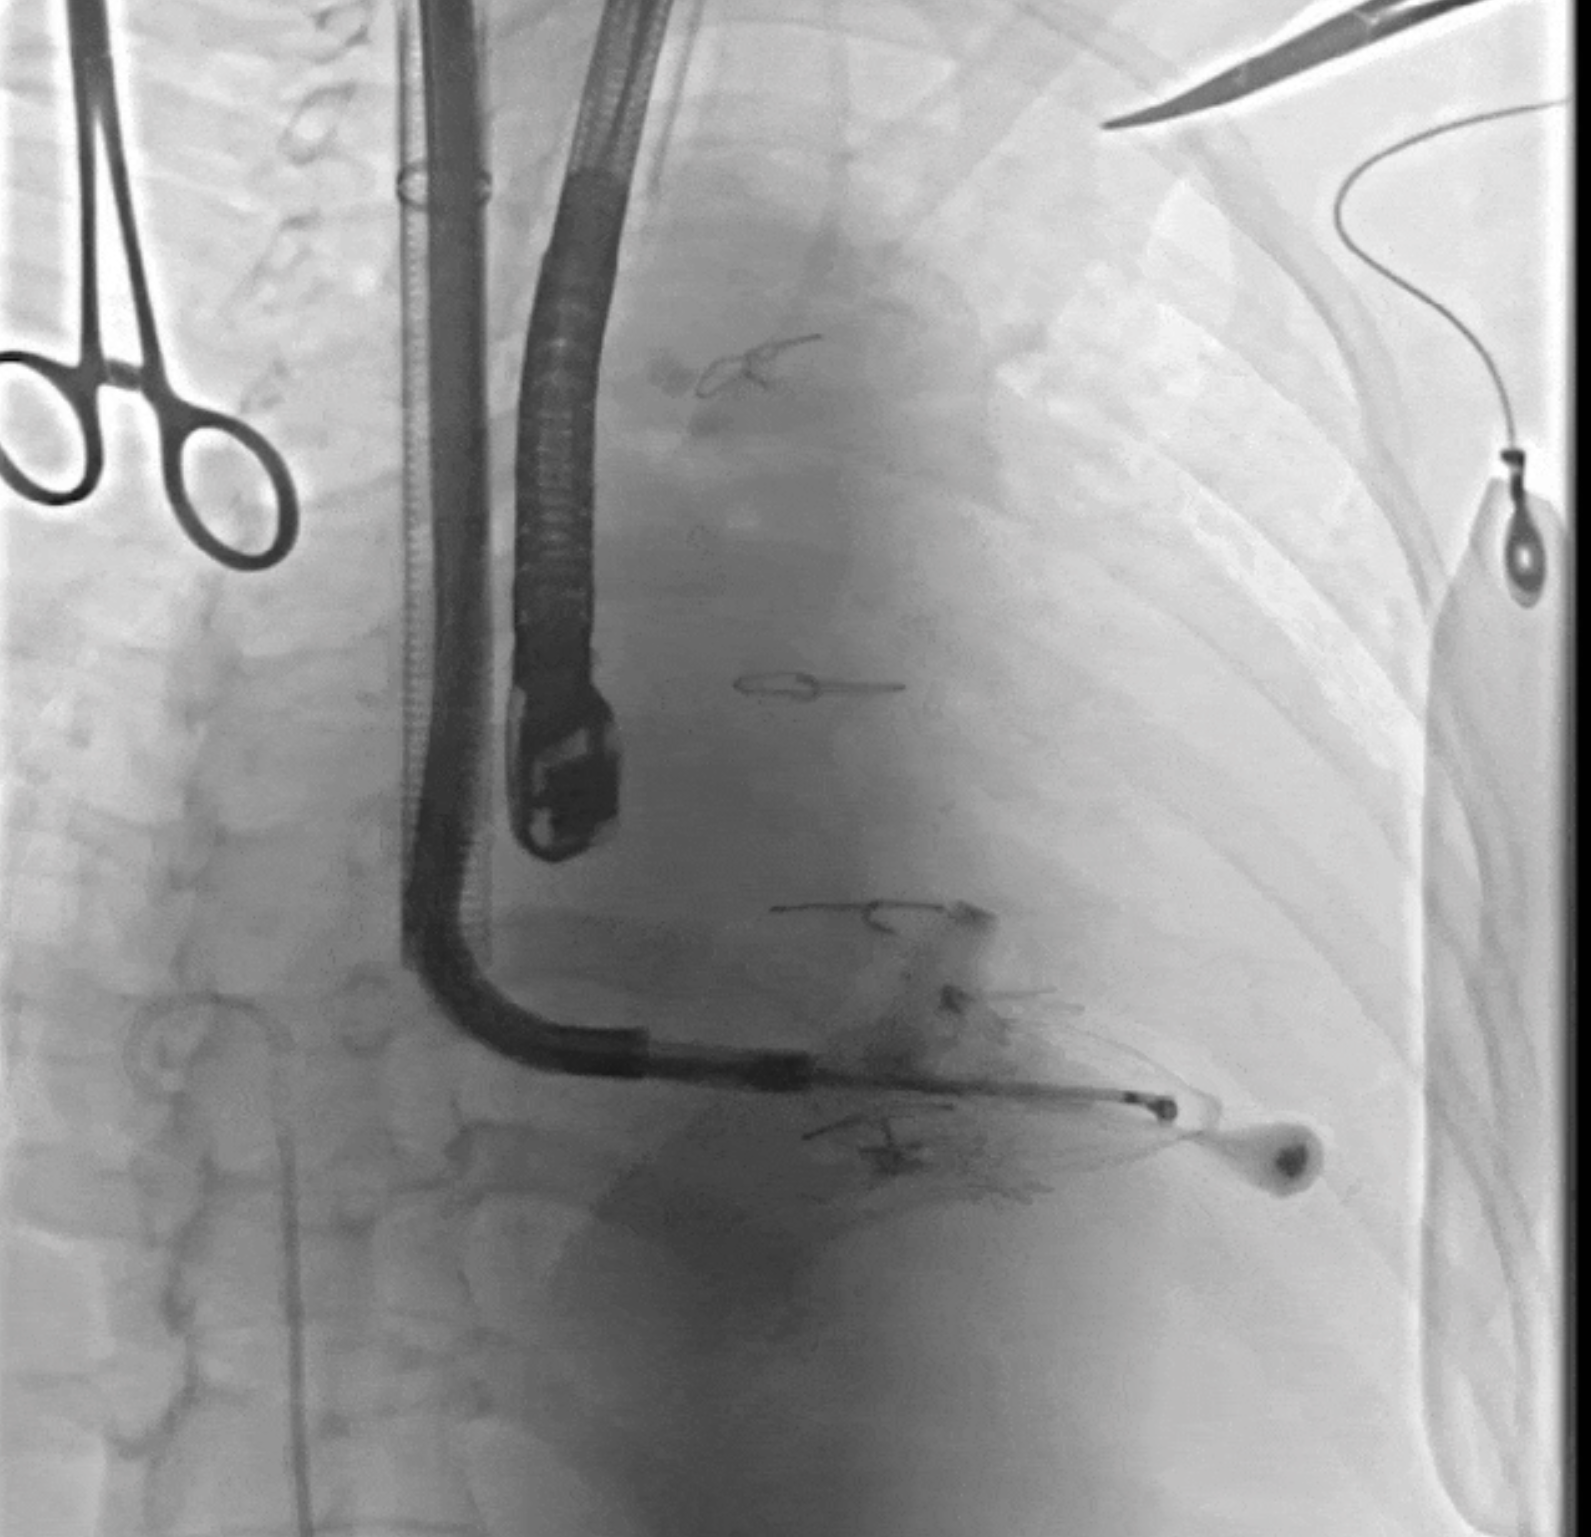

術(shù)中DSA所見:經(jīng)LuX-Valve Plus輸送器系統(tǒng)五向調(diào)整,人工瓣膜同軸良好,夾持件均在瓣葉下。